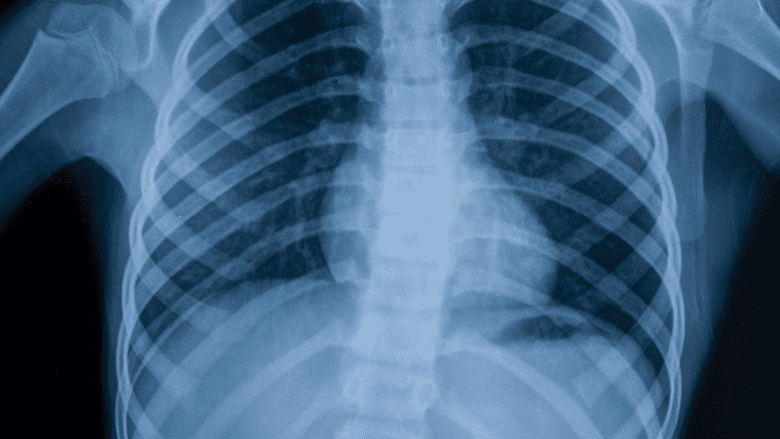

X-rays are helpful in diagnosing spinal arthritis.

X-ray. An x-ray shows signs of degenerative changes in the bones, such as bone spurs at a facet joint, a sign that the bones have tried to compensate for cartilage loss with extra bone growth.

There is a high concentration of nerves radiating from the spine, so even minor cartilage damage or bone spurs detected on an x-ray can translate into a lot of pain if it is in a sensitive spot. It is also possible for a person to experience no pain even though their x-rays to show significant signs of spinal osteoarthritis.